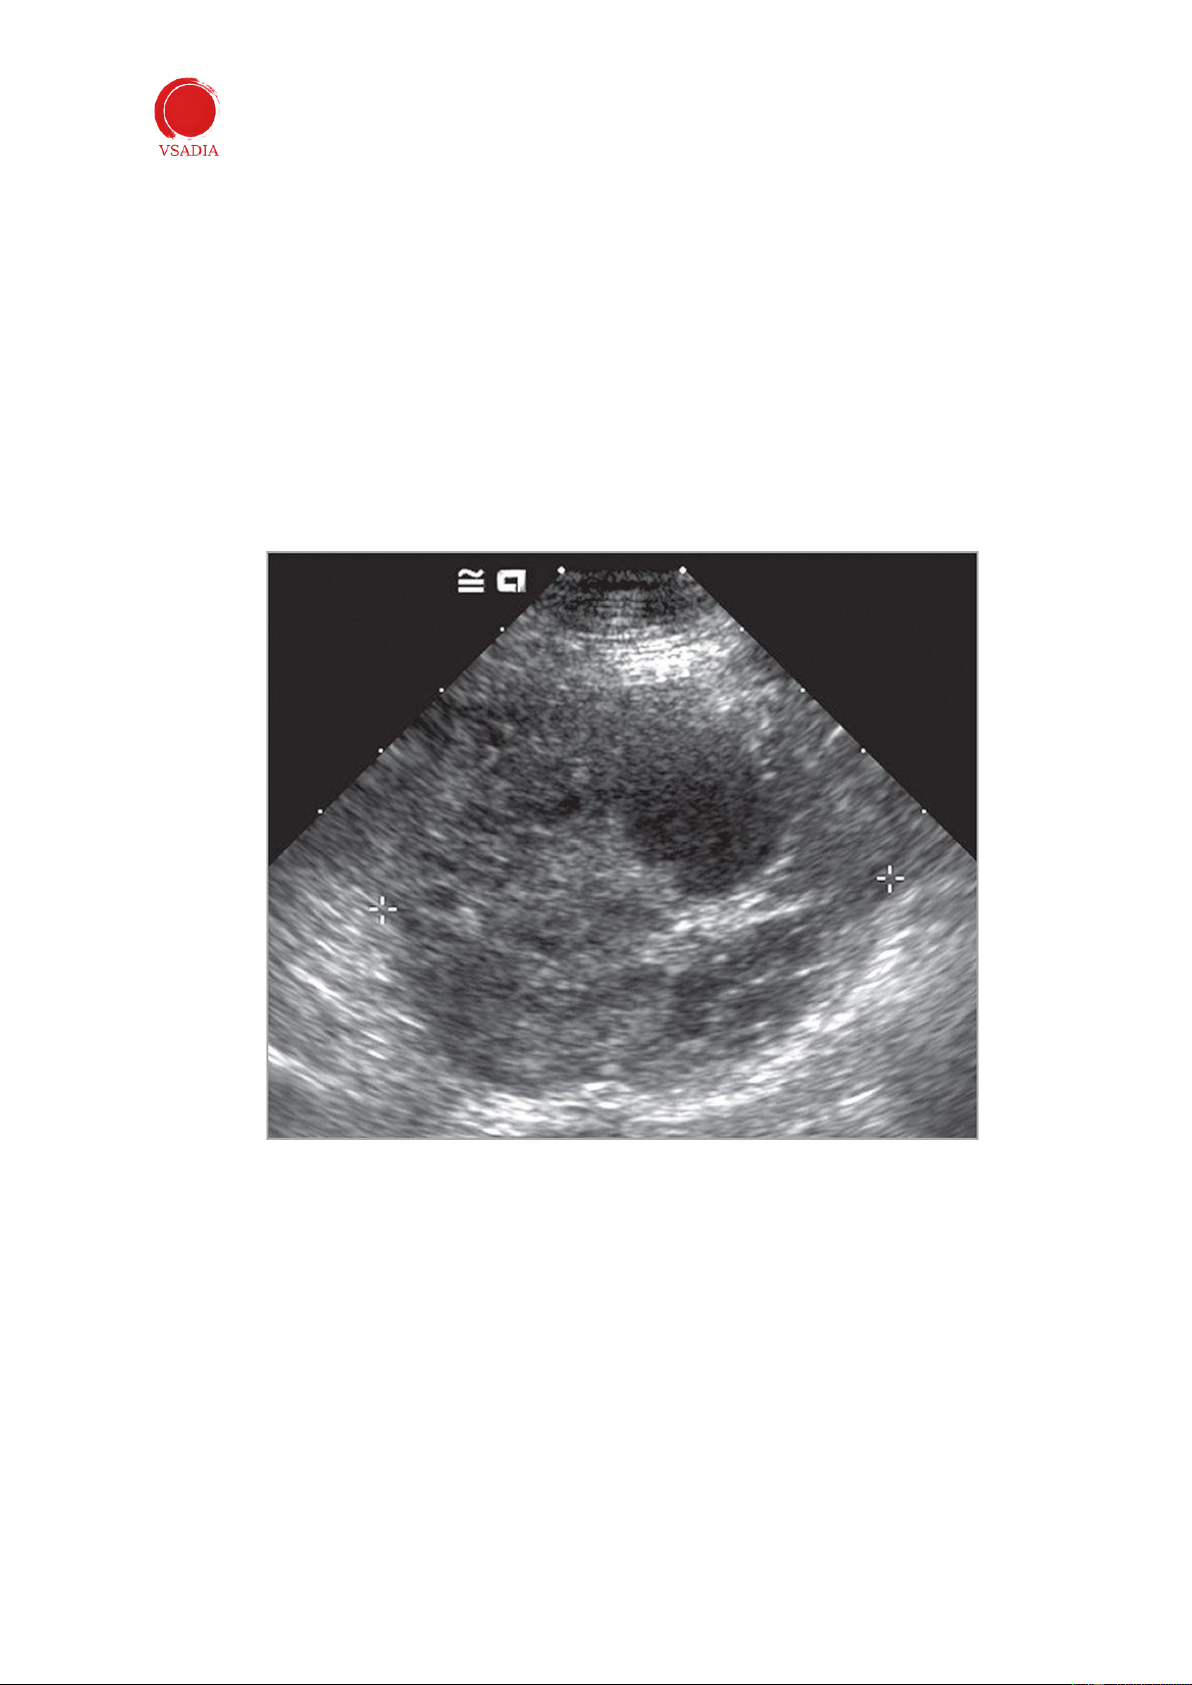

Các khối u buồng trứng (Hình 10) có thể được xác định là các khối của một hoặc cả hai

buồng trứng. Chúng có thể ở dạng rắn, dạng nang hoặc kết hợp. Khối u buồng trứng

lớn có thể xuất hiện ở giữa bụng và thậm chí có thể nằm ở phía bụng dưới. Khi phát

hiện một khối trong ổ bụng, nguồn gốc buồng trứng nên được xem xét dựa trên vị trí

của khối và sự thiếu liên kết với các cơ quan có thể nhìn thấy. Không thể phân biệt loại

u buồng trứng bằng siêu âm. -

Hình 10: Ung thư biểu mô buồng trứng ở chó. Buồng trứng trái tròn, có độ phản âm hỗn hợp và chứa các